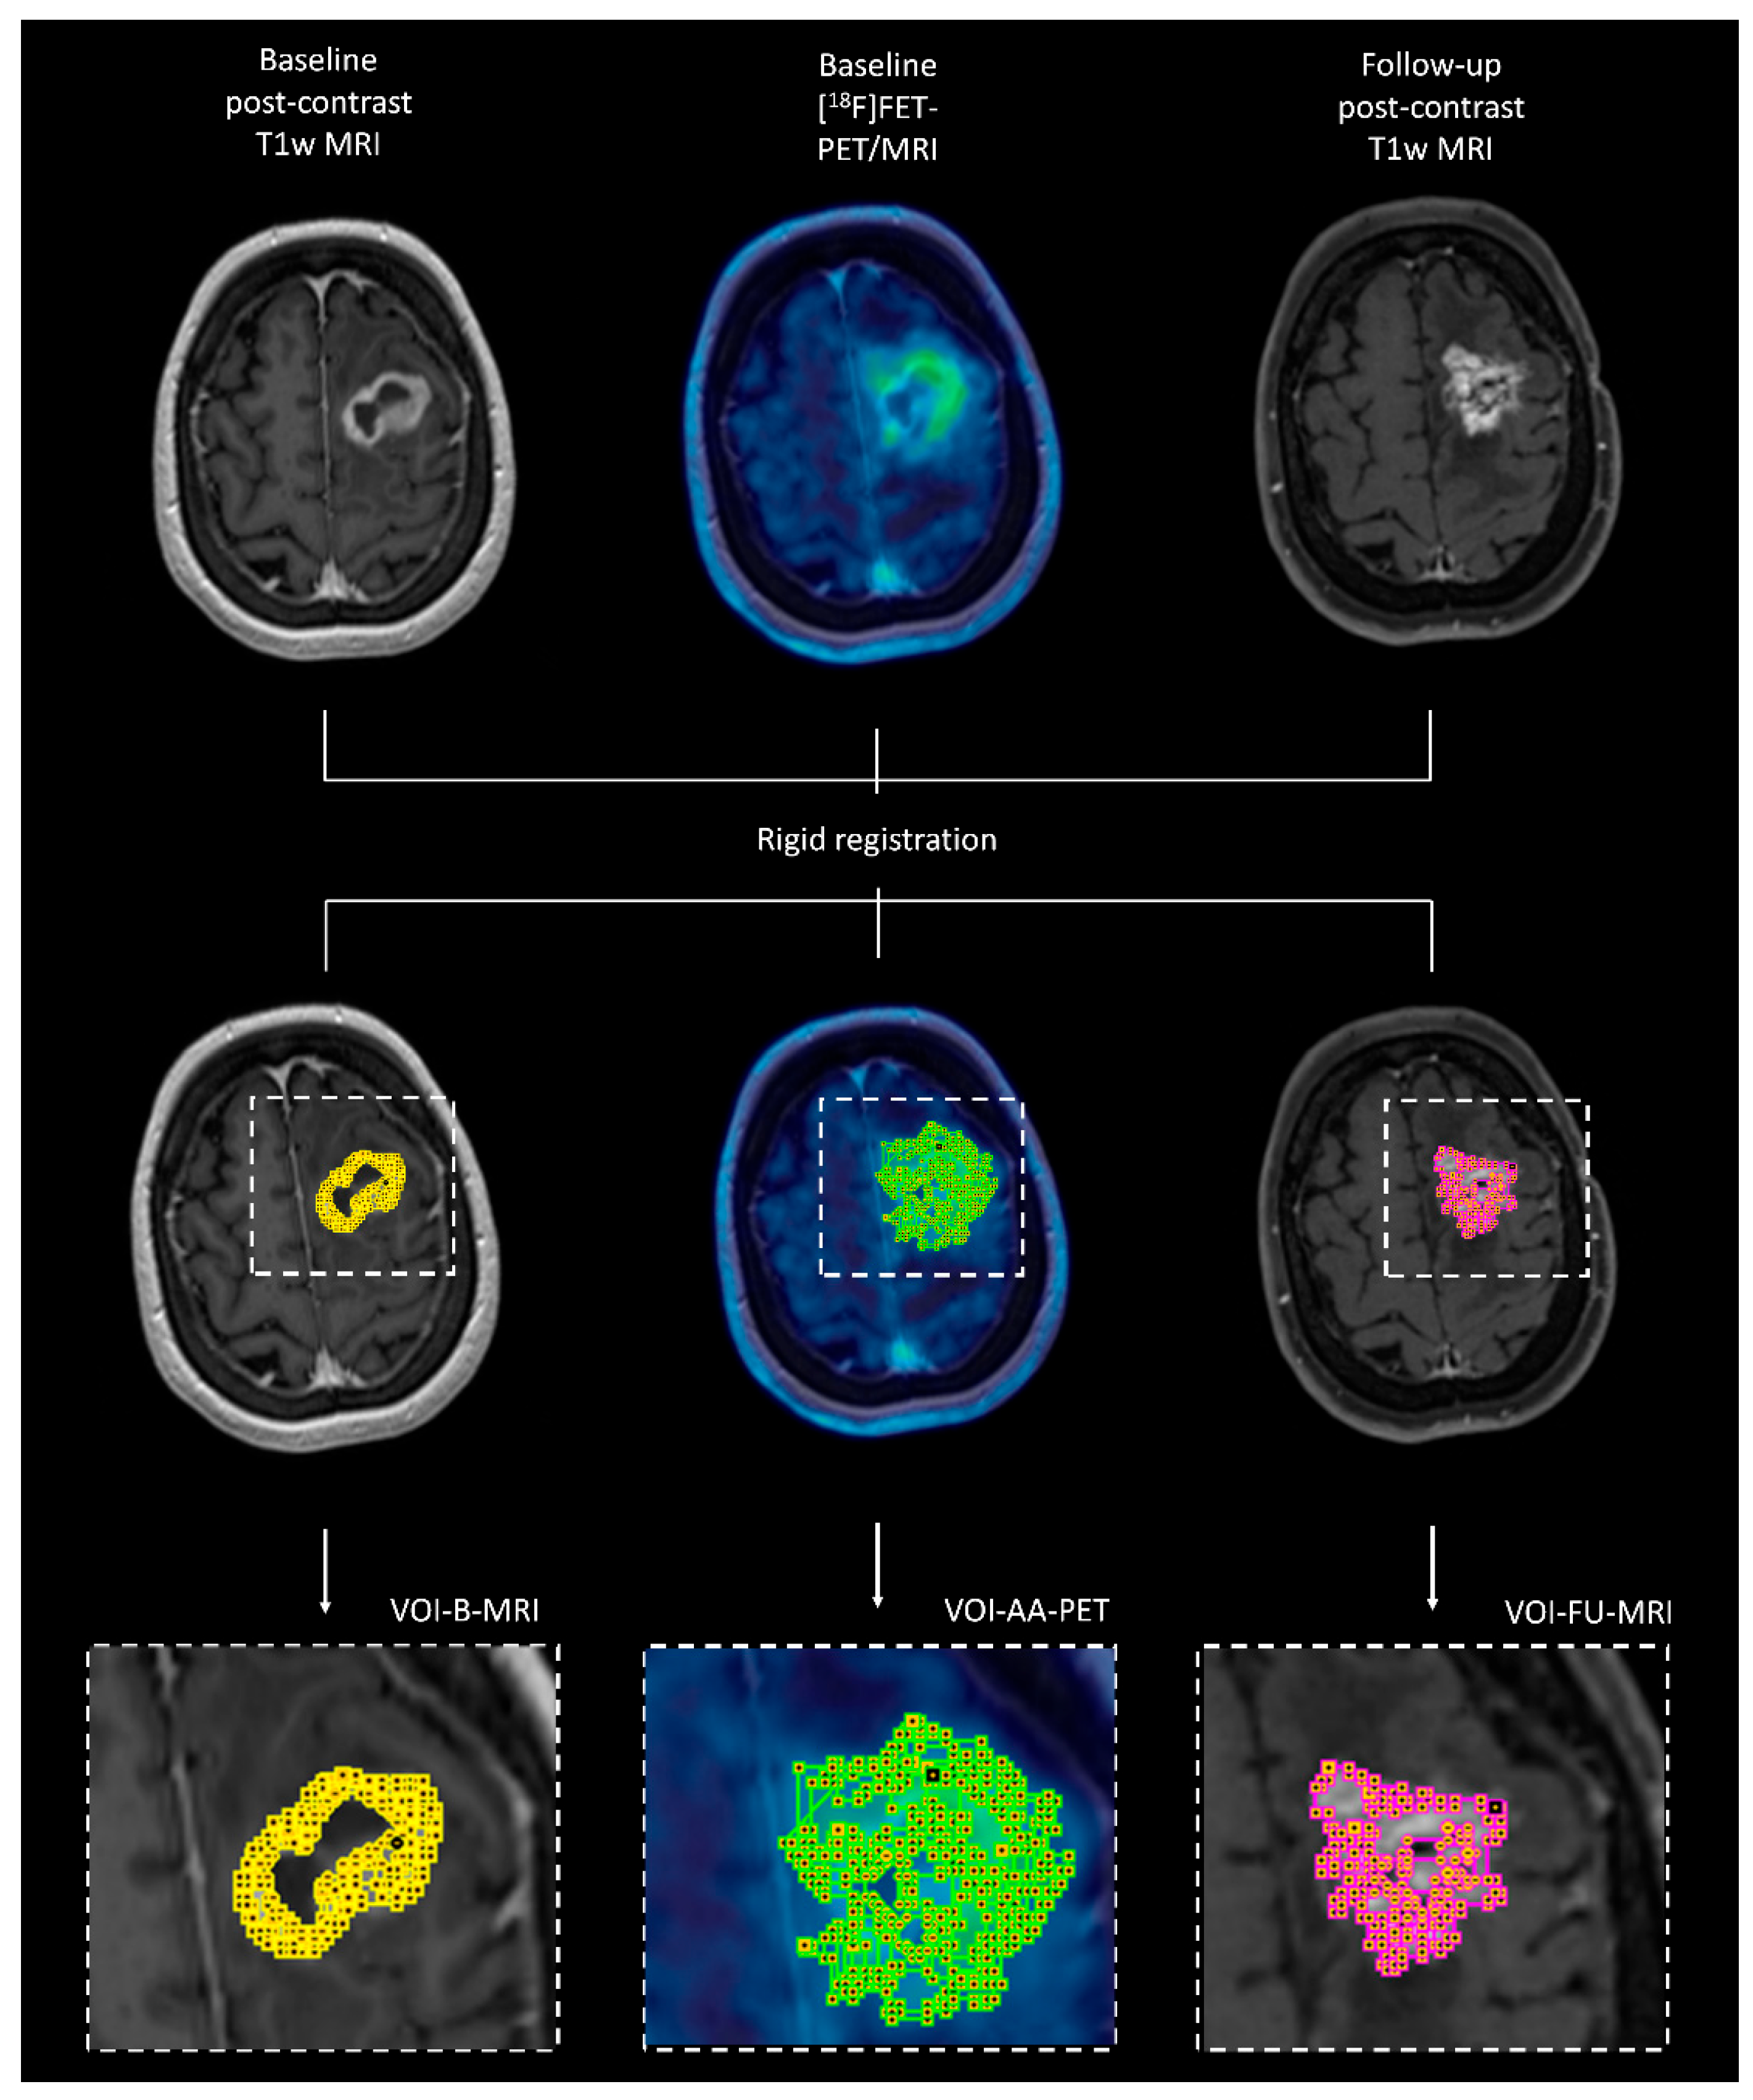

2.4. Co-Registration of Different Imaging Modalities at Different Time Points